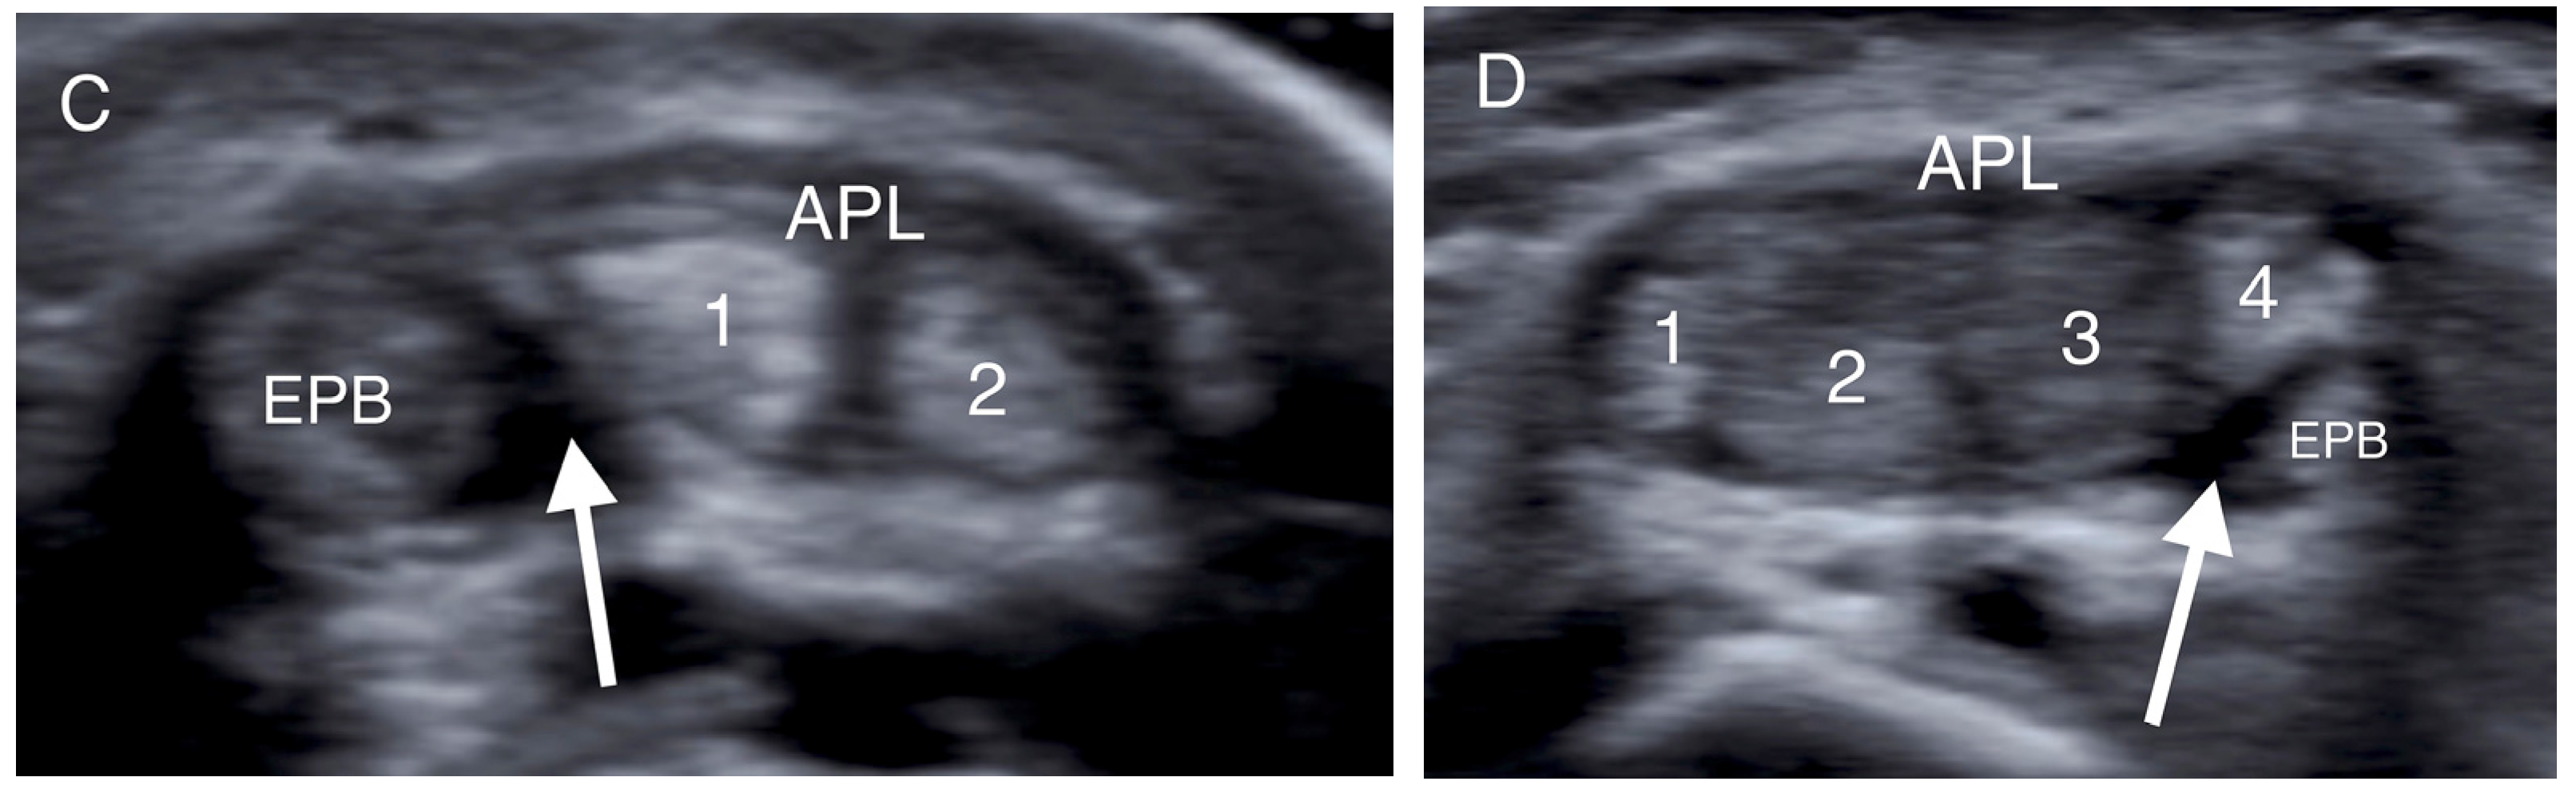

- Choi, S.J.; Ahn, J.H.; Lee, Y.J.; Ryu, D.S.; Lee, J.H.; Jung, S.M.; Park, M.S.; Lee, K.W. De Quervain Disease: US Identification of Anatomic Variations in the First Extensor Compartment with an Emphasis on Subcompartmentalization. Radiology 2011, 260, 480–486. [Google Scholar] [CrossRef]

- Kwon, B.C.; Choi, S.J.; Koh, S.H.; Shin, D.J.; Baek, G.H. Sonographic Identification of the Intracompartmental Septum in de Quervain’s Disease. Clin. Orthop. Relat. Res. 2010, 468, 2129–2134. [Google Scholar] [CrossRef]

- Abi-Rafeh, J.; Mojtahed Jaberi, M.; Kazan, R.; Alabdulkarim, A.; Boily, M.; Thibaudeau, S. Utility of Ultrasonography and Significance of Surgical Anatomy in the Management of de Quervain Disease: A Systematic Review and Meta-Analysis. Plast. Reconstr. Surg. 2022, 149, 420–434. [Google Scholar] [CrossRef] [PubMed]

| Intracompartmental septum | 27 (54%) |

| Double groove | 12 (24%) |